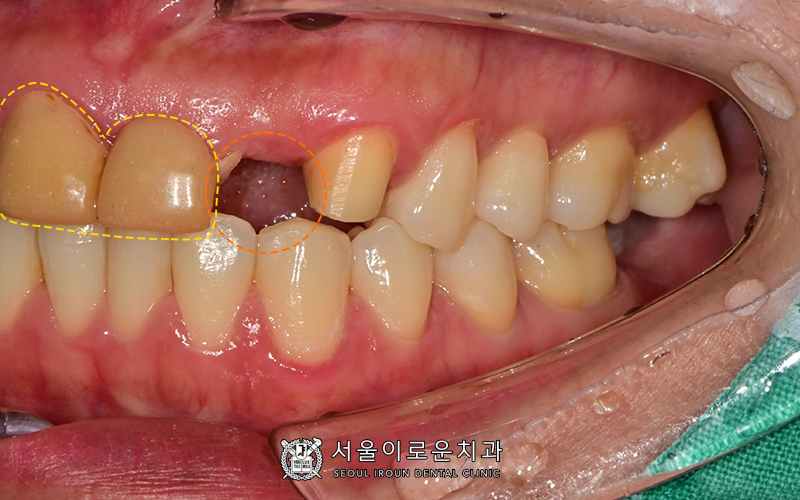

큰 앞니와 송곳니를 보시면

이전에 신경치료를 받으신 상태인 것을

알 수 있는데요.

임상증상이 없는 건전한 상태셨으나,

보철이 아닌 임시치아를

장기간 사용하면서

위생관리가 잘 되지않은 탓에

충치가 관찰되었습니다.

충치치료를 하지 않고

보철을 씌우게 되면,

우식이 계속 진행되면서

차후에 통증 및 염증을 유발하여

치료예후가 좋지 않기 때문에

우식 제거 후 레진으로

치아를 보강하기로 하였습니다!